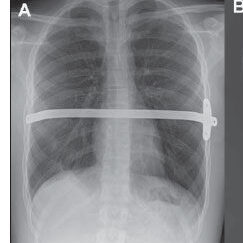

Técnica de Nuss, se usa una barra de metal en forma curvada para que pueda corregir el defecto, el material se retira entre los 18 a 24 meses de la colocación.